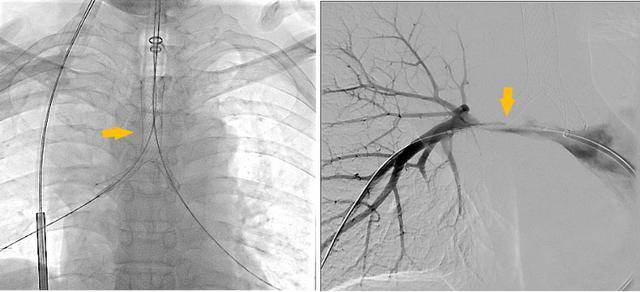

术前受压变窄的右肺动脉和中央气道

手术过程